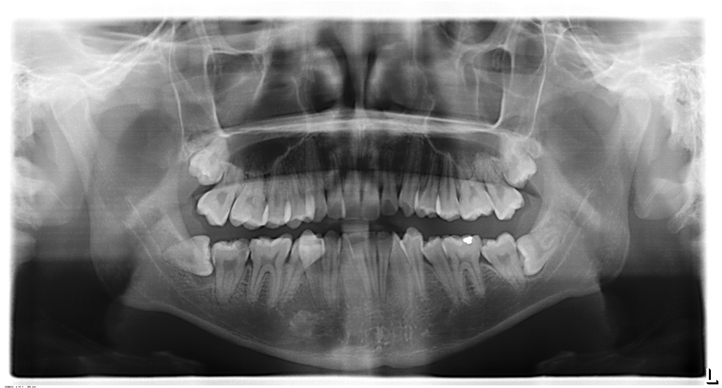

(»çÁø - 1)

±×·¯³ª »ç¶û´Ï°¡ °ø°£ÀÌ ºÎÁ·ÇÏ¿© ÀϺθ¸ ³ª¿À°í ÀϺδ ÀÕ¸ö »À¿¡ ¹¯È÷´Â(»çÁø 1) °æ¿ì³ª ¶§·Î´Â ¹Ù·Î ¾Õ ¾î±Ý´Ï(Á¦2´ë±¸Ä¡)¿¡ °É·Á¼ ´õ ÀÌ»ó ¸ÍÃâÇÏÁö ¸øÇÏ°í ¾Õ´Ï ÈĸéÀ» ¾Ð¹ÚÇÏ´Â ÇüÅ·Π´©¿ö ÀÖ´Â ¼öÆòÁöÄ¡(»çÁø 2) ÇüÅ·Π³ª±âµµ ÇÕ´Ï´Ù.